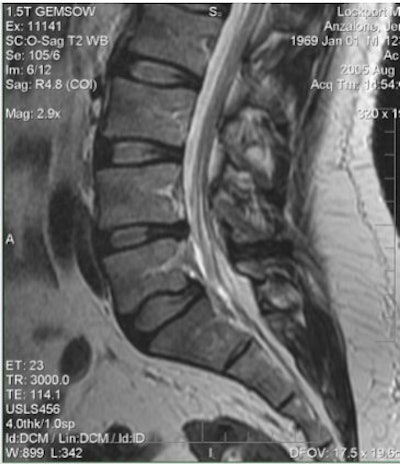

![]() |

| Above, preaxial loaded. Below, axial-loaded image. Central subligamentous disk herniation and discogenic disease at L5-S1 impressing the thecal sac only after axial loading is applied. L4-L5 bulging, discogenic disease, and a central subligamentous disk herniation impressing on the thecal sac. Bulging and discogenic disease at all other levels. |